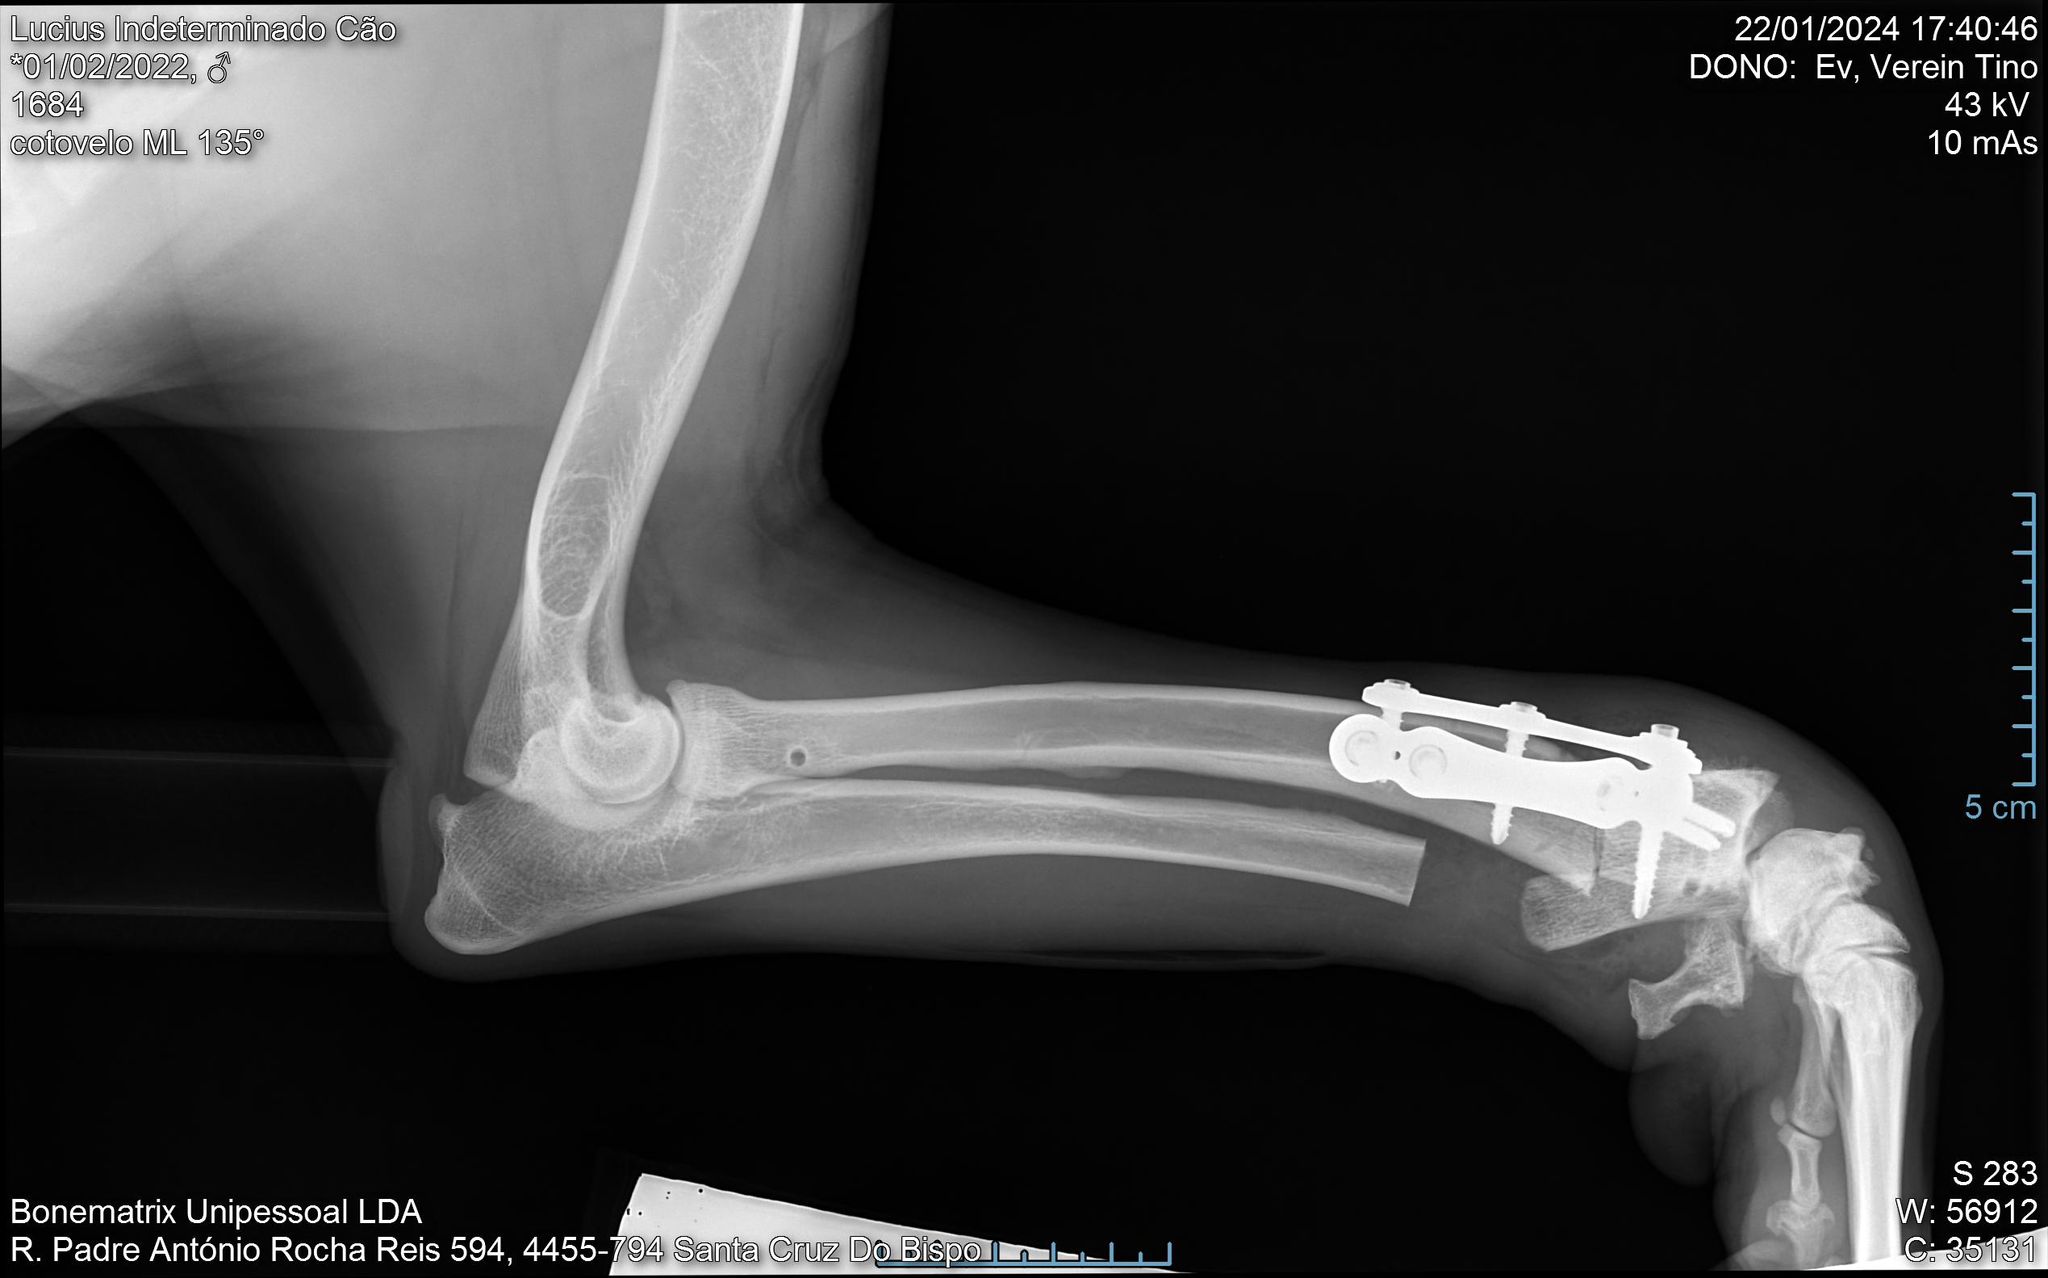

Lucius hat eine Deformation am linken Vorderbein. Er muss als Welpe von einem Auto angefahren worden sein und sich dabei 2 Knochen gebrochen haben. Einer der Knochen hörte auf zu wachsen, der andere jedoch nicht, daher die deformierte Pfote. Zusätzlich führt das noch zu einer Deformation der Wirbelsäule, was dem jungen Hund manchmal Schmerzen bereitet.

Nach Aussage mehrerer Spezialisten kann der Knochen durch eine orthopädische Operation korrigiert werden. Zuerst muss mit Hilfe von CT-Scans eine personalisierte Prothese nach Maß angefertigt werden. Diese wird dann operativ von 3 Ärzten eingesetzt. Die Kosten für die Operation und die Untersuchungen werden momentan auf ca. 3.000 € geschätzt.

Lucius wurde am 22.1. operiert.

Lucius musste leider zwischenzeitlich an seinem Bein operiert werden. Sein Körper hat die implantierte Prothese abgestoßen. Diese musste nun entfernt werden. Der Arzt meinte, dass Lucius auch inzwischen ohne sie klar kommt. Alles ist gut verlaufen und er ist wieder in seiner Pension und so wild wie immer. :-)